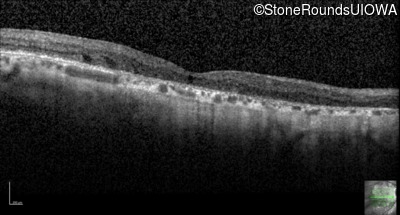

Foveal Hypoplasia (IIIG)

Diagnosis & molecular findings

Disease Gene Allele 1 variant(s) Allele 2 variant(s) Inheritance mode

Foveal Hypoplasia PAX6 Pro76Leu CCG>CTG   AD